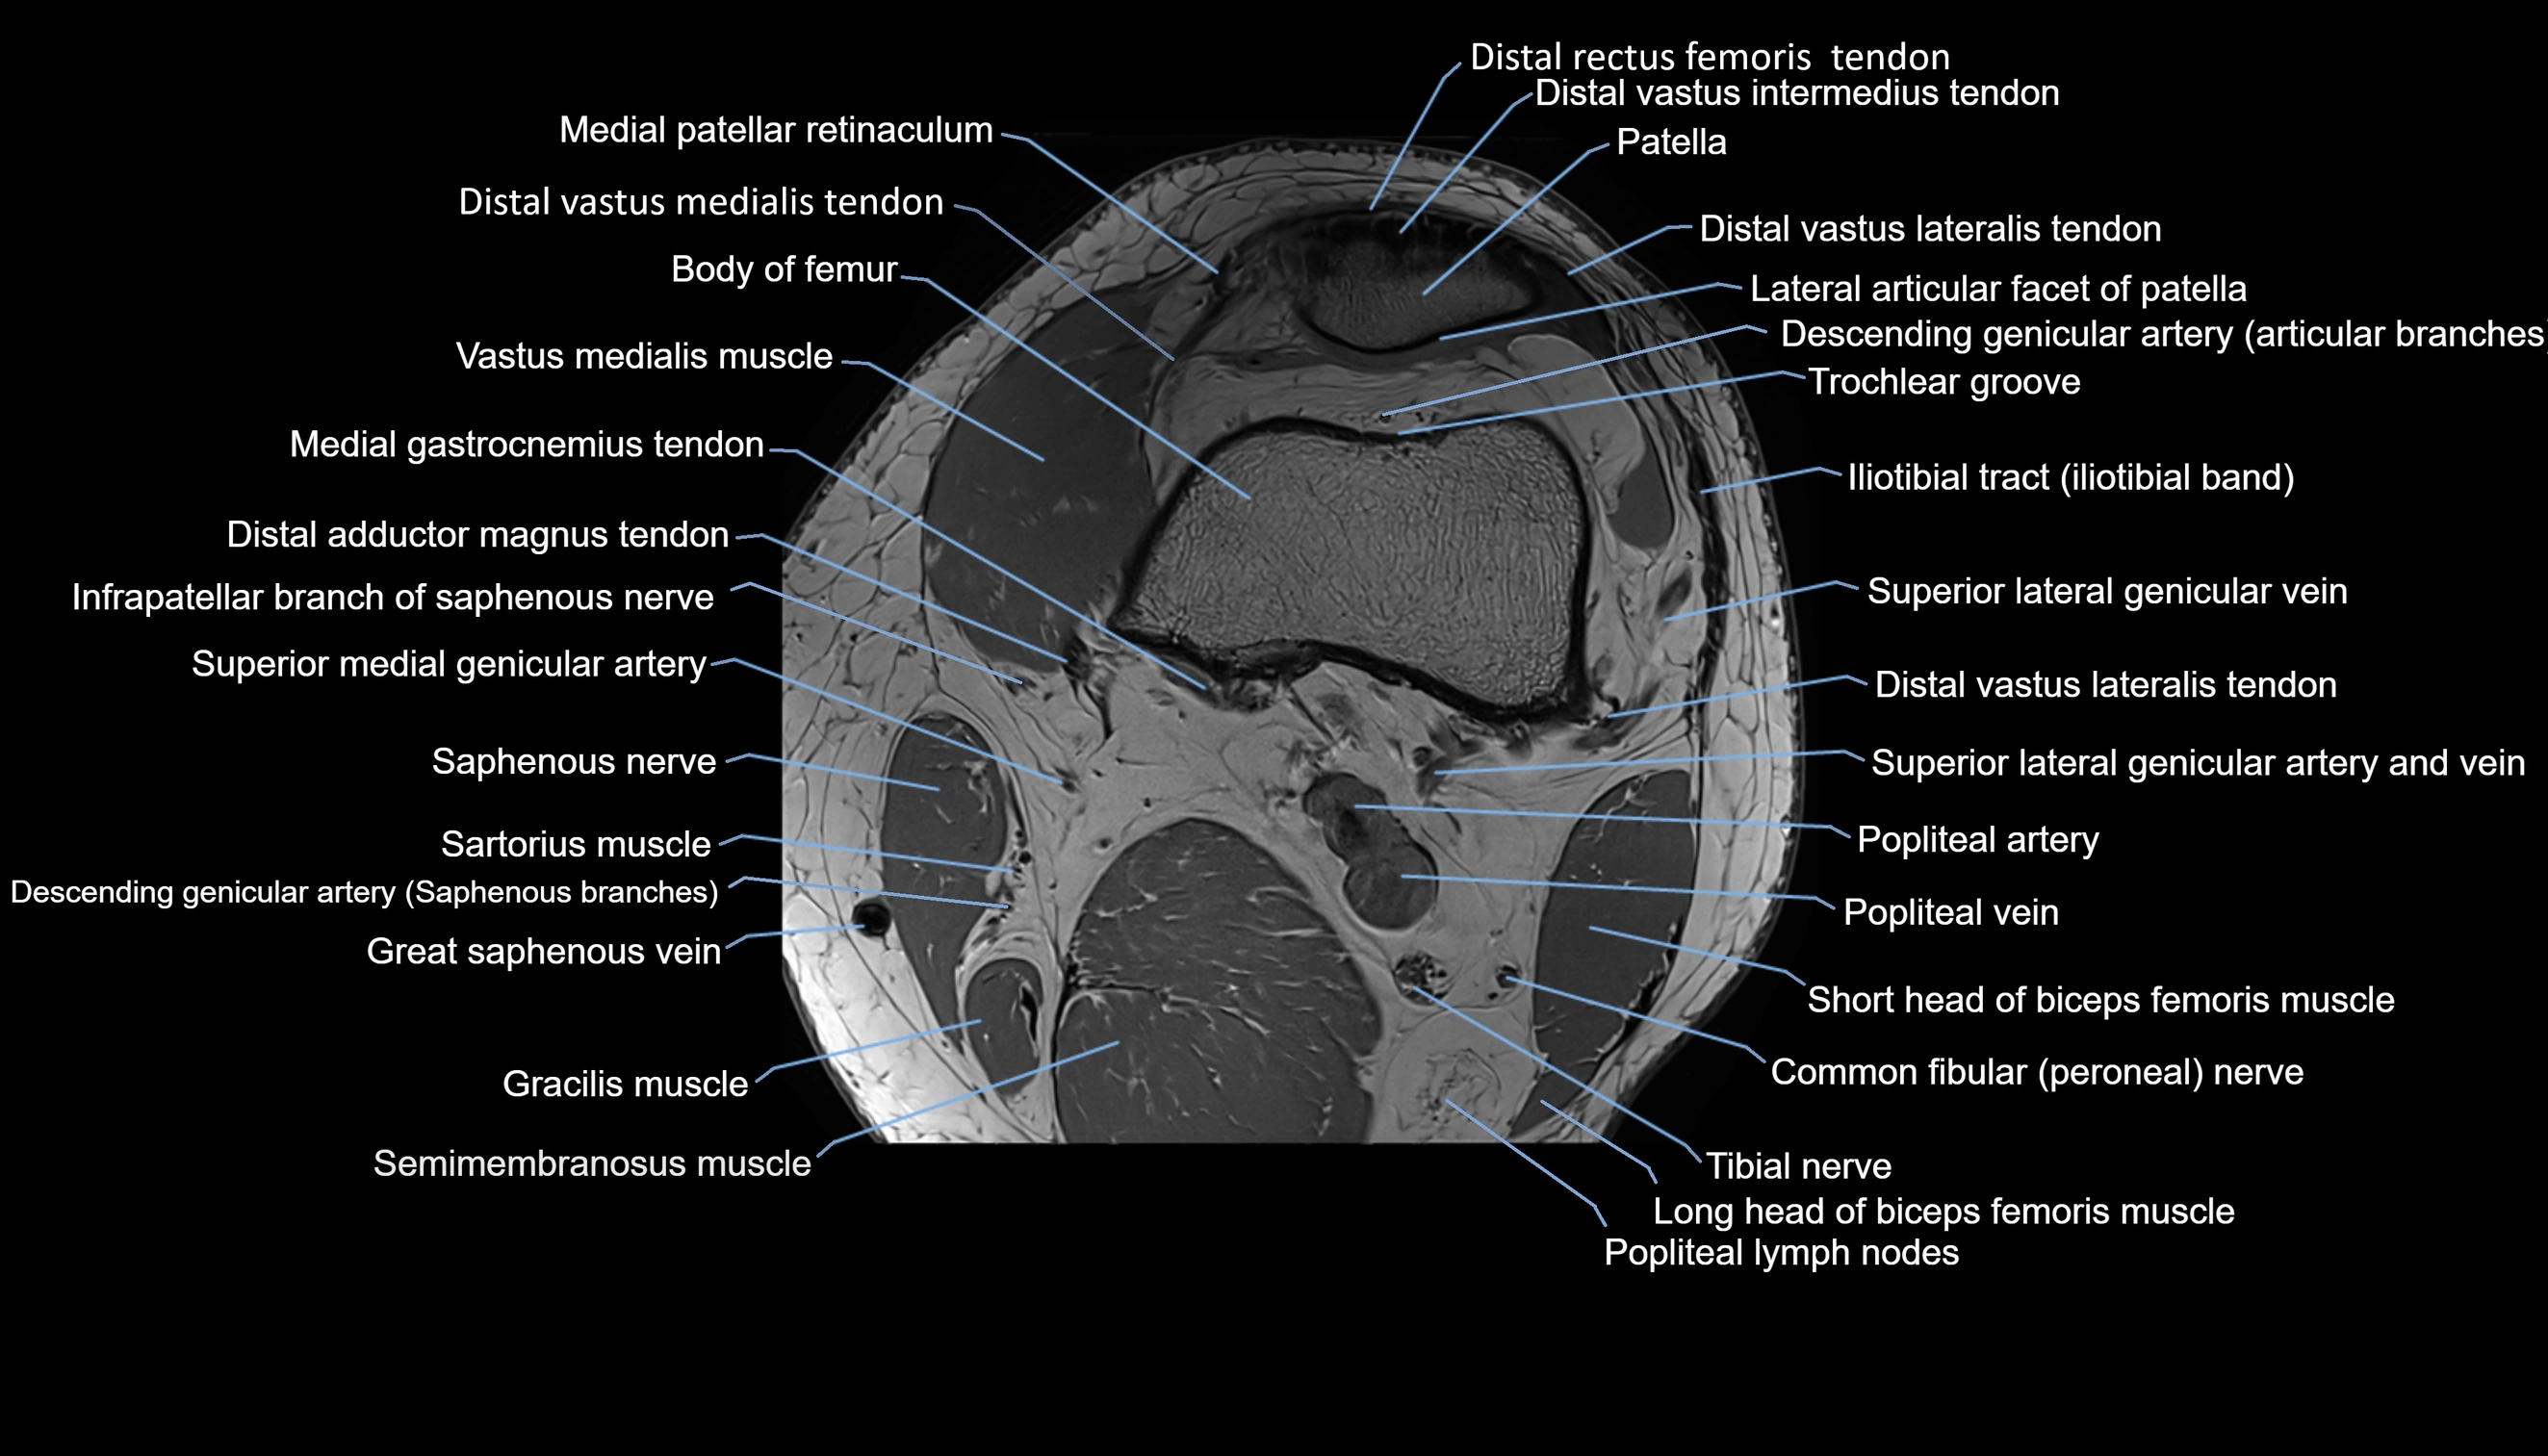

- Descending genicular artery (Articular branches)

- Descending genicular artery (Saphenous branch)

- Distal adductor magnus tendon

- Distal rectus femoris tendon

- Distal vastus intermedius tendon

- Distal vastus lateralis tendon

- Distal vastus medialis tendon

- Infrapatellar branch of saphenous nerve

- Infrapatellar fat pad

- Lateral articular facet of patella

- Medial gastrocnemius tendon

- Medial patellar retinaculum

- Patella

- Popliteal artery

- Popliteal lymph nodes

- Popliteal vein

- Saphenous nerve

- Sartorius muscle

- Superior lateral genicular artery

- Superior lateral genicular vein

- Trochlear groove

- Vastus Lateralis Obliquus Muscle

- Vastus lateralis muscle

- Vastus medialis muscle

- great saphenous vein